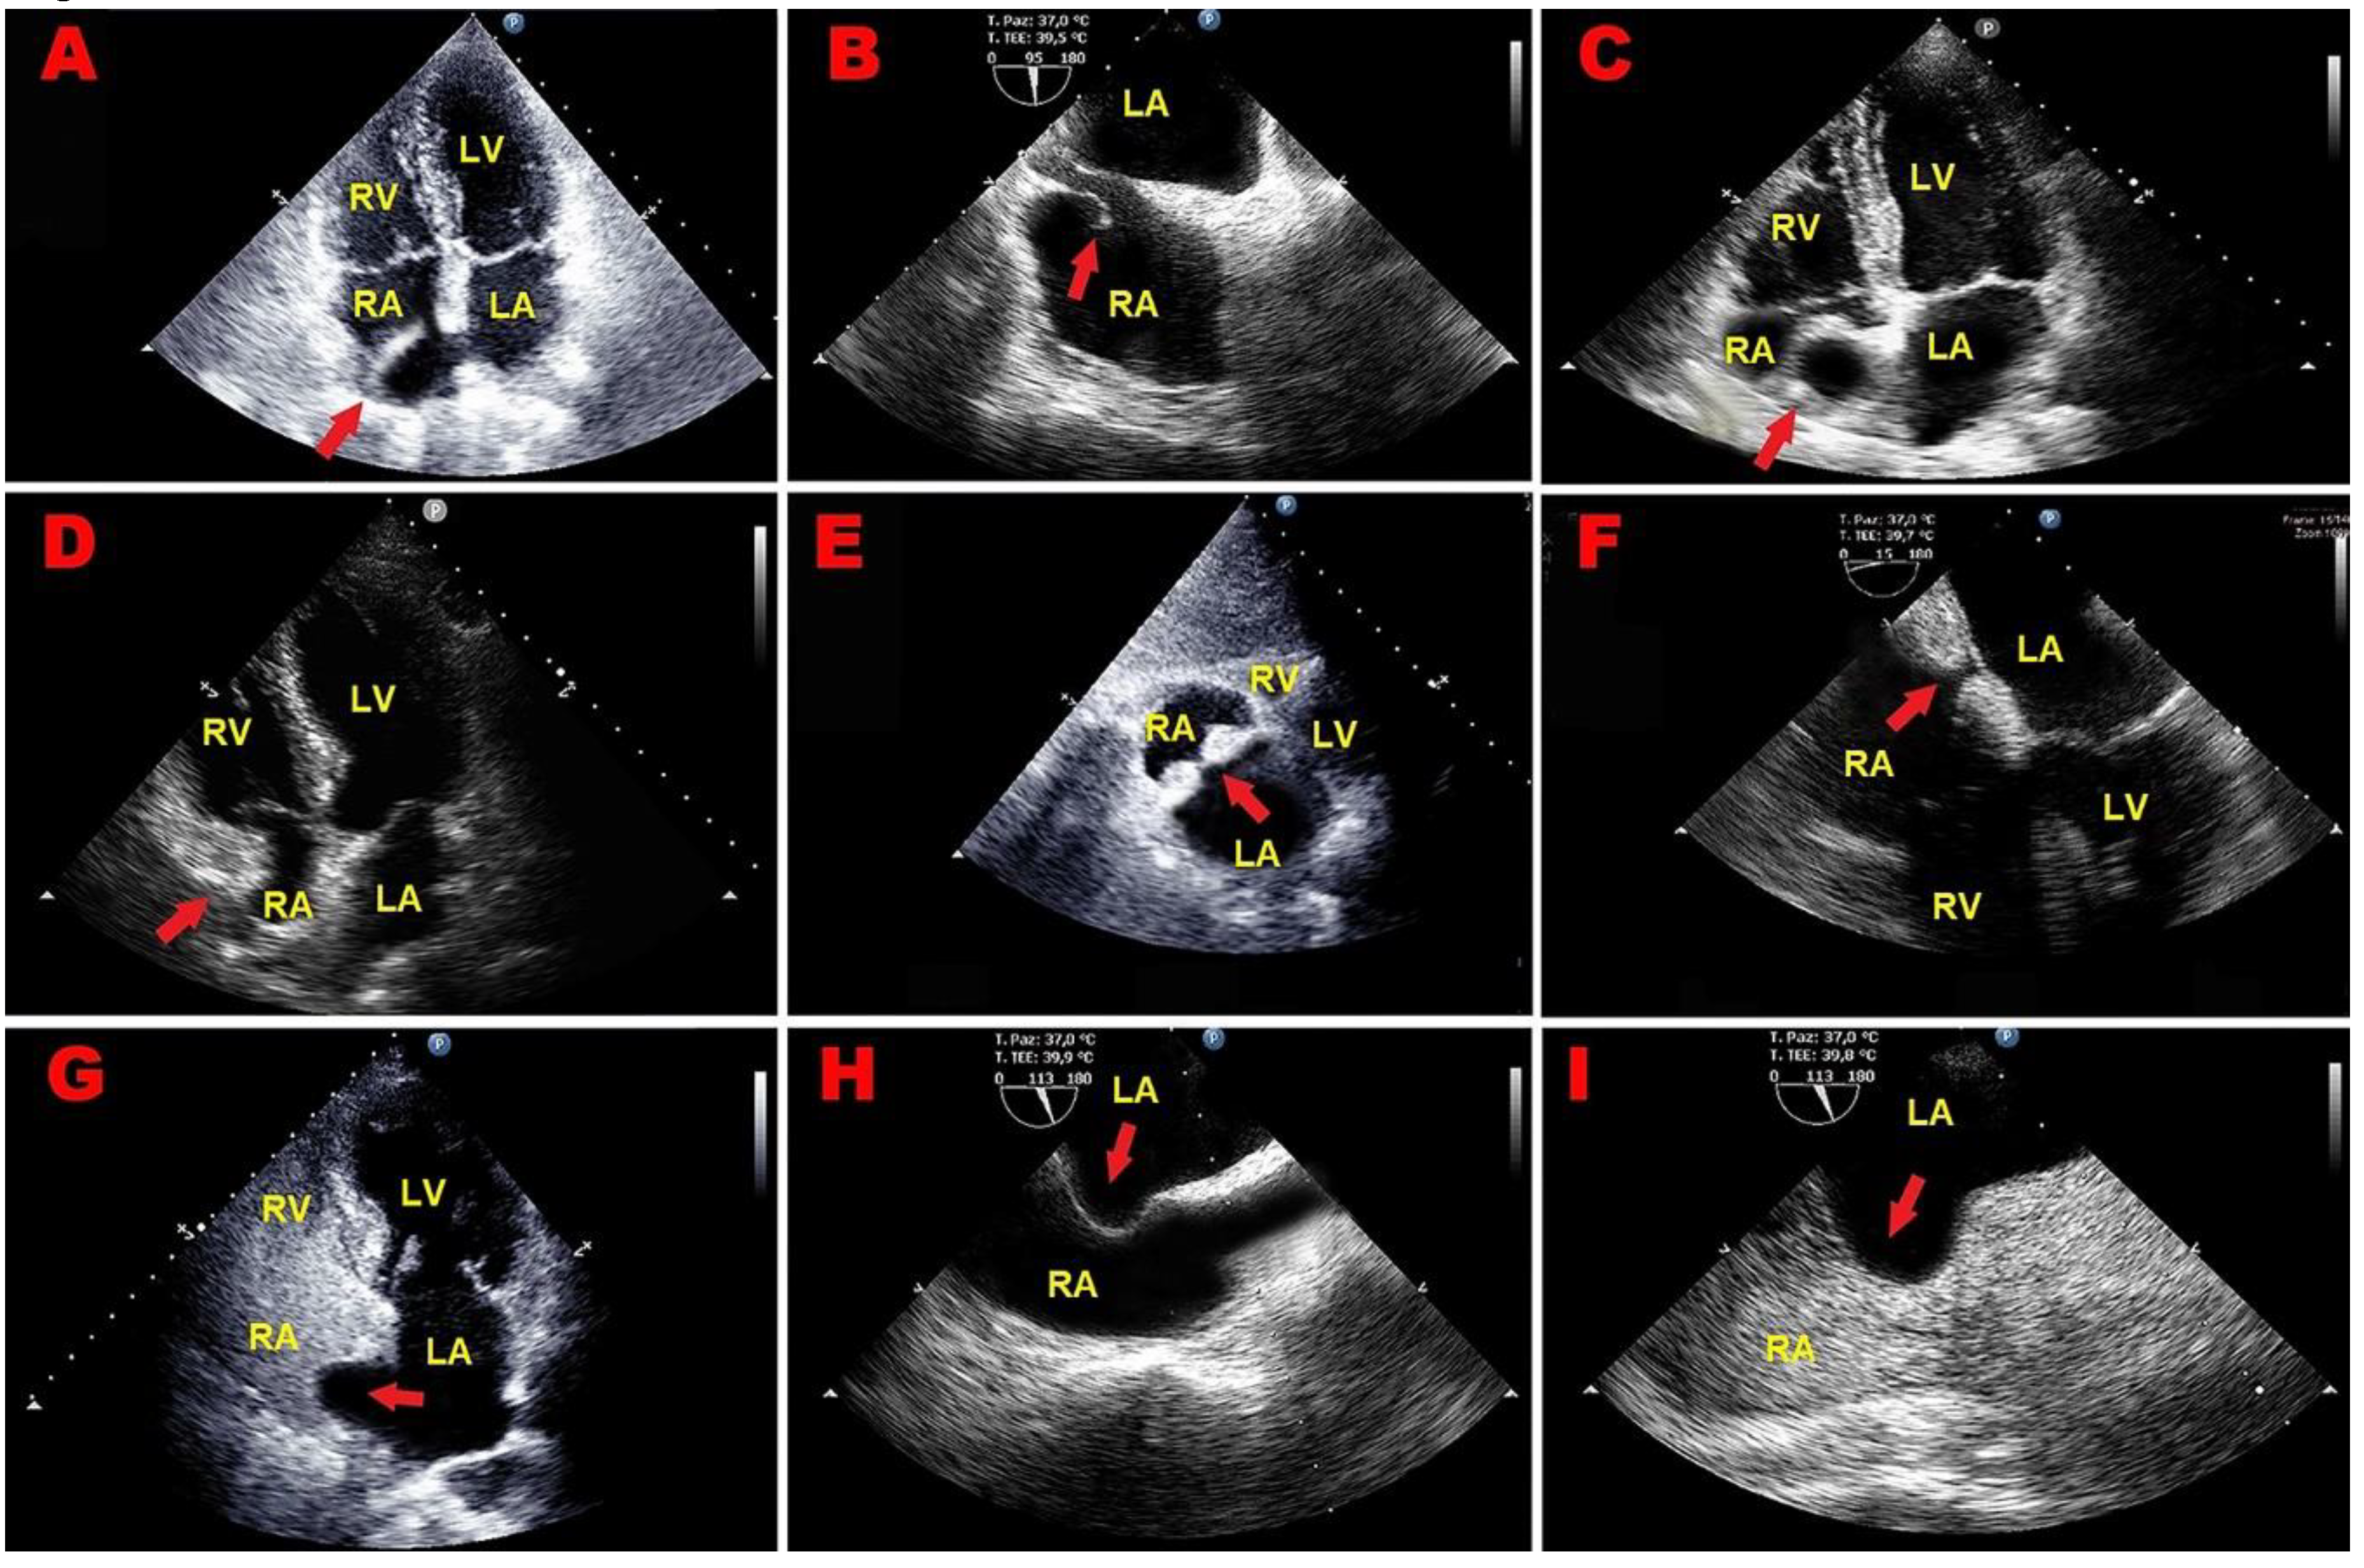

2.1. Clinical Case 1

2.2. Clinical Case 2

3.1. Right Atrial Masses

3.2. Right Atrial Pseudomasses